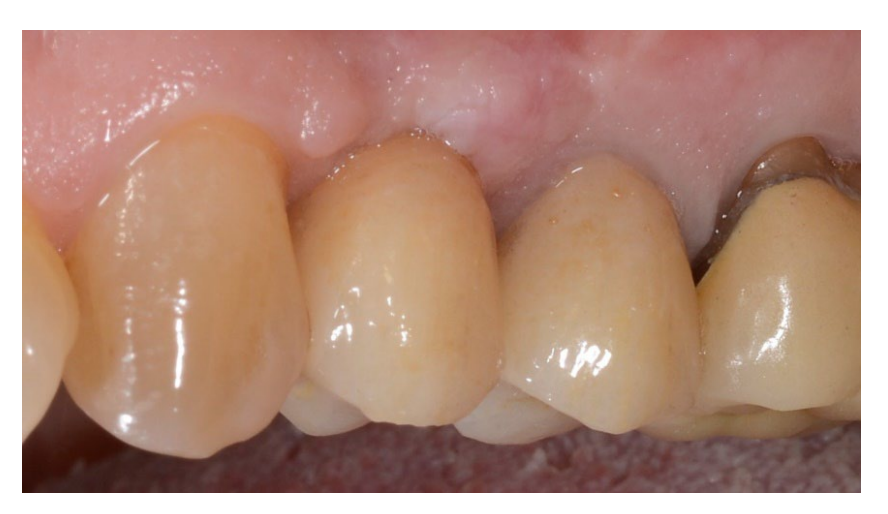

In both groups, six to eight months after tooth extraction (group A and B, respectively), dental implants (Premium, Sweden and Martina, Due Carrare, PD, Italy) were placed. In none of the cases was it necessary to carry out an additional GBR. The amount of bone was judged sufficient to place an implant of 3.8 mm of diameter and 10 to 11.5 mm of length. Flap design was performed according to the clinical scenario and the patient’s requirements. Before implant site preparation, a calibrated trephine bur with a 3.0 mm external diameter was used to collect a core sample for histologic analysis. The implants were submerged for three months. Three months after implant placement, a screw-retained temporary restoration was delivered. Finally, two to three months after initial loading, a definitive, screw-retained, CAD/CAM, metal-free restoration was delivered. Occlusion was adjusted, and follow-up visits were scheduled every four months.